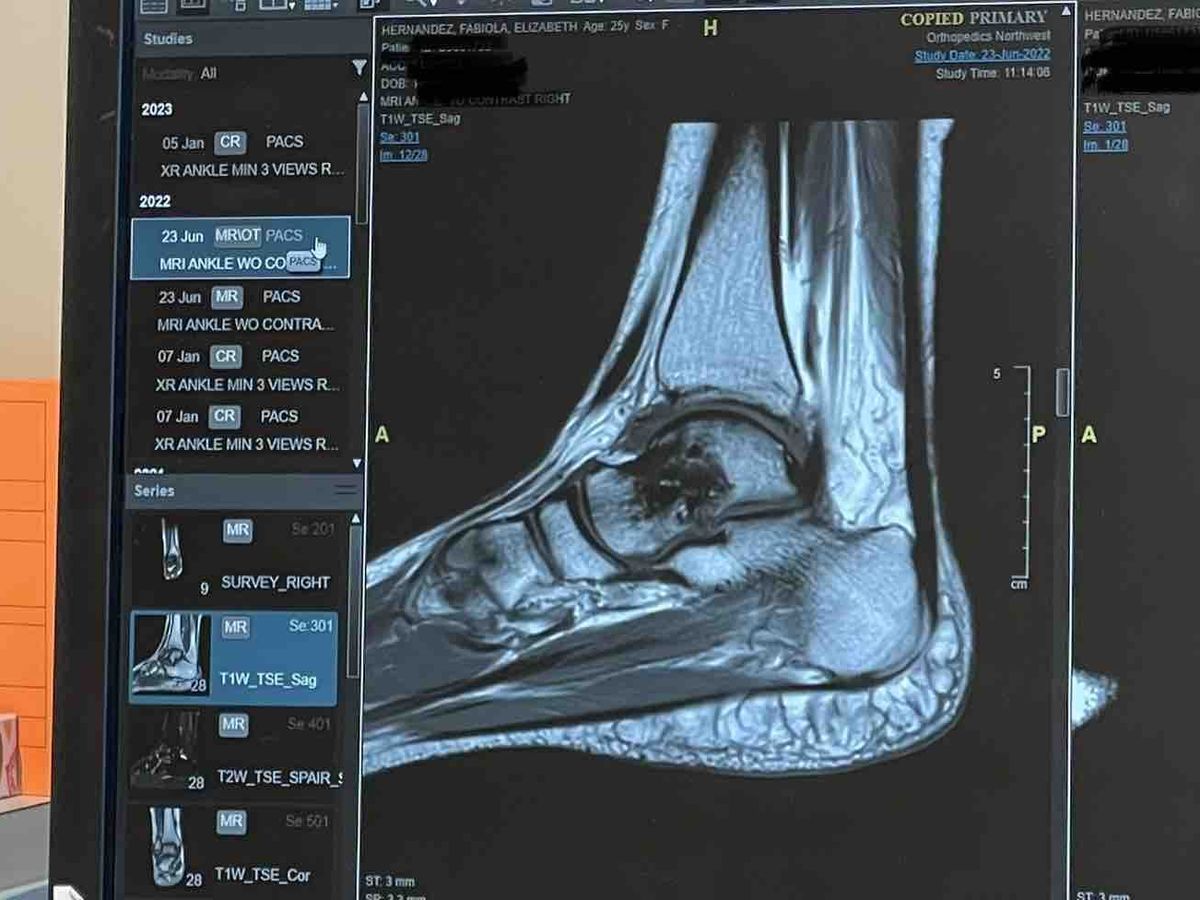

Long story short: I injured myself back on 5-11-21 and the hospital initially thought it was a tiny fracture. I had to wait a week to be seen by the only ankle orthopedic doctor in town, it was determined I sprained my ankle. I was told to be in a boot for a few weeks and to begin with physical therapy. If this wasn’t in the middle of Covid I wouldn’t have hesitated to go to Seattle for a second opinion/treatment but I decided to stay put and go with the dr here at home in Yakima. After a few weeks of PT, I returned to the Dr and kept pressing that something was not right, that it wasn’t just an ankle sprain. Finally an MRI was ordered and once results were read (3 months after injury) I still had a partially torn ligament and small bone bruise. One month later, I had surgery on 9-23-21. The surgeon came out and told my support person in the lobby “it was worse than I was expecting” and it’s only gotten worse since then. My small bone bruise has developed into Avascular Necrosis (lack of blood flow to the bone) resulting in arthritis. After seeing three different doctors in the Seattle area, being instructed to rest as much as possible, being on crutches and a knee scooter, being prescribed a bone stimulator (not covered by insurance) and now being given what feels like a real option— a hybrid prosthetic called an Exosym. I was finally able to walk without pain for the first time in nearly two years. I couldn’t believe it… But this is why I’m reaching out to you, I need your help to access this device. I was quoted $4081.86 for the Exosym and I need to have half of that down by my appointment next week or I have to further push back accessing this relief. If you’re able to give any amount, it would be greatly appreciated. And if you’re a person of faith, please say a prayer for me that this is the medical intervention that restores my body and that I’m able to meet this need. I thank you all for your love and support as I begin to open up about my journey to healing.

I severely sprained my ankle back on May 11, 2021 when I was out with my pup and a friend. I was being a good dog owner and “cleaning up” after my puppy. Rather than walking my dog around the retaining wall I figured I could quickly climb over the wall to get to the trash. A 30 second shortcut has cost me so much… I had so much regret, I have told myself a million times “I should have just walked around that wall” with the help of my amazing therapist I’ve come to accept that had I “walked around that wall” I still may have hurt myself and I would have told myself “I should have climbed over that wall”. Due to Covid I decided it would be best and the most responsible thing to stay in Yakima for treatment rather than seek out medical care in the Seattle area. And I also I wanted to have faith that Yakima didn’t have the poor medical care everyone always talks negatively about but the horrible reality of medical system being for profit & being in a rural-like community there is only one ankle orthopedic doctor. I was brushed over, I wasn’t listened to when I expressed something was wrong, I was made to feel I didn’t know what I was talking about when listening to my body and that “it wasn’t that bad”. After repeat visits, many physical therapy appointments (2x a week for 4 weeks) and months passing from the initial injury, Dr’s PA requested an MRI in July, the MRI was done in early August and appointment to go over the results wasn’t until late August. The MRI revealed I had a partially torn ligament explaining the reason for prolonged ankle instability, they also found a SMALL bone bruise. Surgery was scheduled for 9-23-21 to repair the ligament.

Surgery day comes and I’m hopeful this will be the real beginning to healing in addition the the 6 weeks of physical therapy I was going to have to go through after once approved. I planned for this the best I could, I budgeted to the best of my ability for surgery and 6 weeks of PT. When the physician came out of my surgery, he found my support person in the waiting room to update them and he himself said “it was worse than I was expecting.” That is not what you want to hear AFTER this person just operated on you. After a year of me continuing to say something is not right, we finally did an updated MRI in Yakima, the results were bad, very bad. It was discovered that my small bone bruise had worsened after surgery, I had lost blood flow to the bone and developed Avascular Necrosis. I now have arthritis in the Talus bone. I’ve been asked if I’m an alcoholic, cancer survivor, steroid user and none of those apply to me; further indicating arthritis of that one specific bone was likely caused by my injury or my care. I now have the ankle of a 60 year person. After my original surgeon went over the MRI results months after surgery (May 2022) he told me to go get a second opinion and when I asked “okay, I will. But what are WE going to do next?” He responded with “we’ll talk about it at a later date but for now go get a second opinion” that was the last time I spoke to him as called once a week for four weeks straight and never got a call back from his assistants or the clinic. My original surgeon, for a lack of a better term, ghosted me.